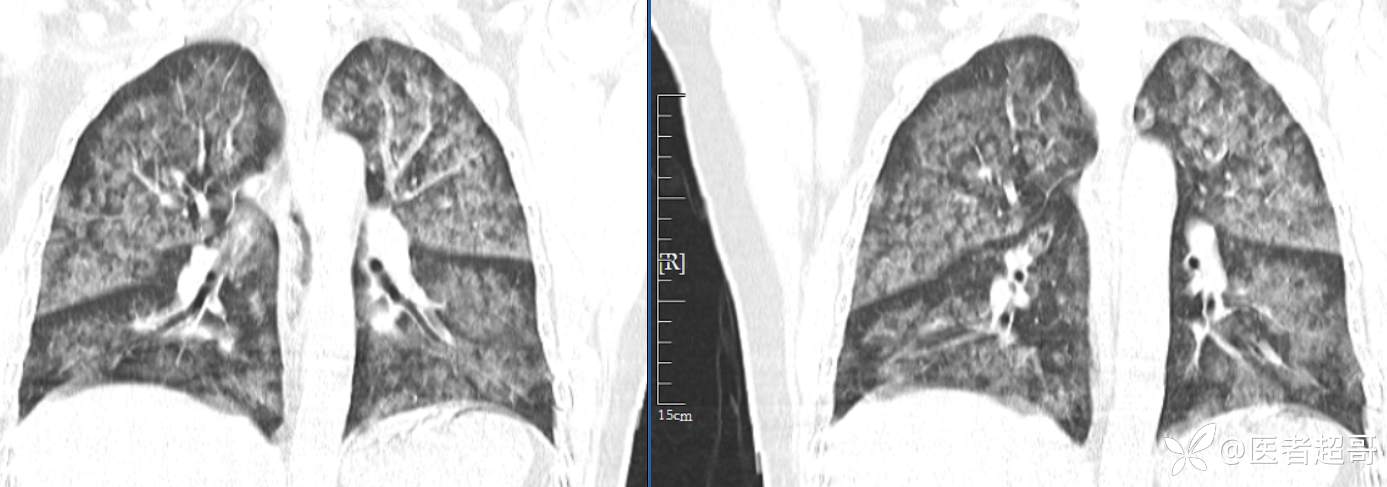

【影诊笔记574】胸痛就诊检查,发现双肺多发高密度,请赏析!

患者性别:女

患者年龄:47岁

主诉:胸痛就诊

简要病史:因“胸痛就诊”,行冠脉CTA检查,数小时后出现高热,伴畏寒寒战、气喘,暗红色泡沫样痰。

急性肺水肿 (17)